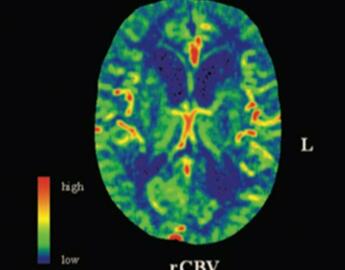

Example of perfusion changes

Postictal Hypoperfusion

Seizures are not just an electrical phenomena, they also alter how the brain circulates blood and which regions are fed. We are currently exploring long-term changes in brain vascular dynamics following seizures.